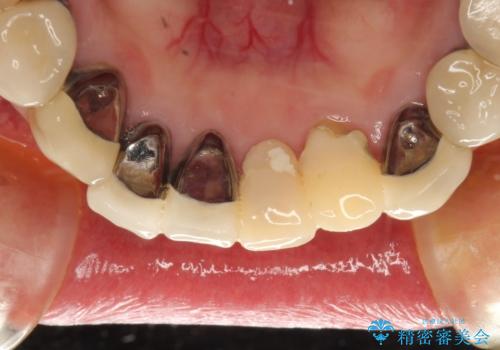

- 下顎の前歯に激痛を覚えて来院された患者様です。

取り急ぎ下顎前歯数歯の根管治療を、銀座しらゆり歯科医院長の林先生にお願いし、それ以外に気になっている、不自然な色調のクラウン、金属部分が見えてブラッシングがしにくいインプラント補綴、口元の突出感、出血のしやすい歯周ポケットなど、全てを解決するための治療を行うこととしました。